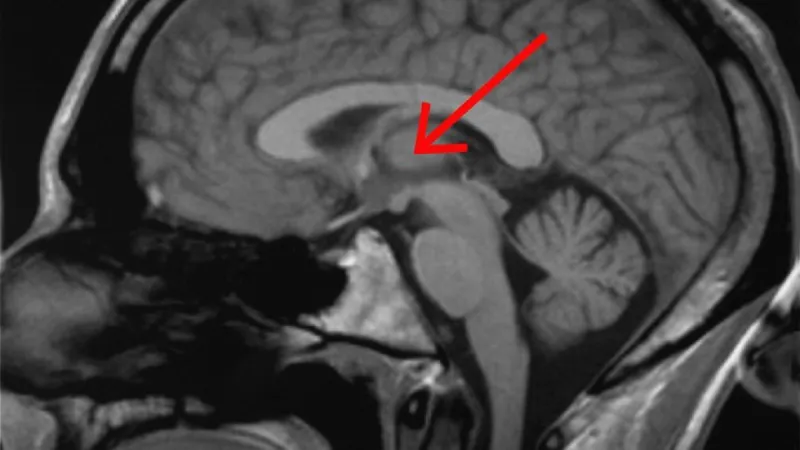

Oran má teď v mozku umístěné dvě elektrody, které vedou až do hloubky thalamu, což je část mozku, jež je mimo jiné zodpovědná za přenášení vzruchů a smyslových vjemů dále v mozku. Elektrody pak vedou k samotnému přístroji.

Tento neurostimulátor vypadá jako tenoučký, asi třícentimetrový čtvereček; je umístěný do otvoru vyhloubeného v chlapcově lebce. Zařízení spotřebuje poměrně dost energie, ale vědci přišli na to, jak ho nabíjet, aniž by to mladíkovi příliš komplikovalo život: elektřinu získává z bezdrátových sluchátek, zatímco s nimi například sleduje televizi.